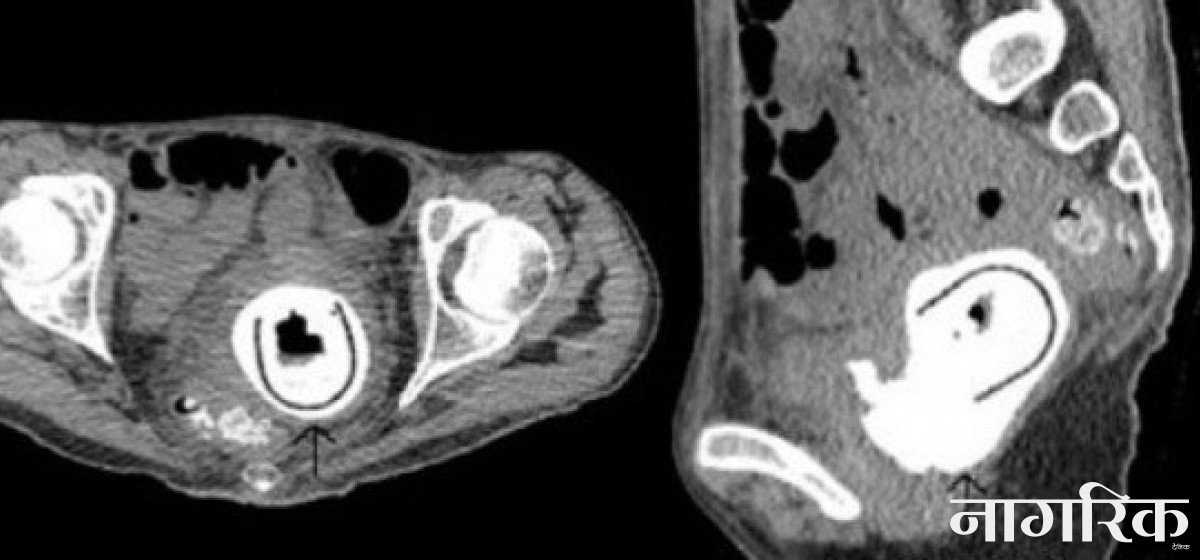

अझ खोजी गर्दा थाहा भयो, सेक्स टोय उनको योनीमा अड्किएर बसेको १० वर्ष पूरा भइसकेको रहेछ। शल्यक्रिया गरेर सेक्स टोय उनको योनीबाट झिकिएको छ।

यो अनौठो घटनाको विस्तृत जानकारी जर्नल अफ सेक्सुअल मेडिसिनमा प्रकाशित भएको छ। जर्नलमा प्रकाशित प्रतिवेदन उद्धृत गर्दै तयार पारिएको समाचारमा भनिएको छ, 'योनीमा सेक्स टोय रहेको पत्ता लाग्दा बिरामी जतिबेला जेसुकै हुने अवस्थामा पुगिसकेकी थिइन्। टोयले मुत्रथैलीलाई थुनेर राखेको थियो र यसले किड्नीमा नराम्रो असर पुर्याइसकेको थियो। योनीभित्र टोय छ भन्ने पत्ता नलागेको भए, जतिबेला पनि अप्रिय घटना घट्न सक्थ्यो।'